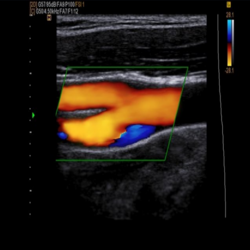

Ultrasonography Services